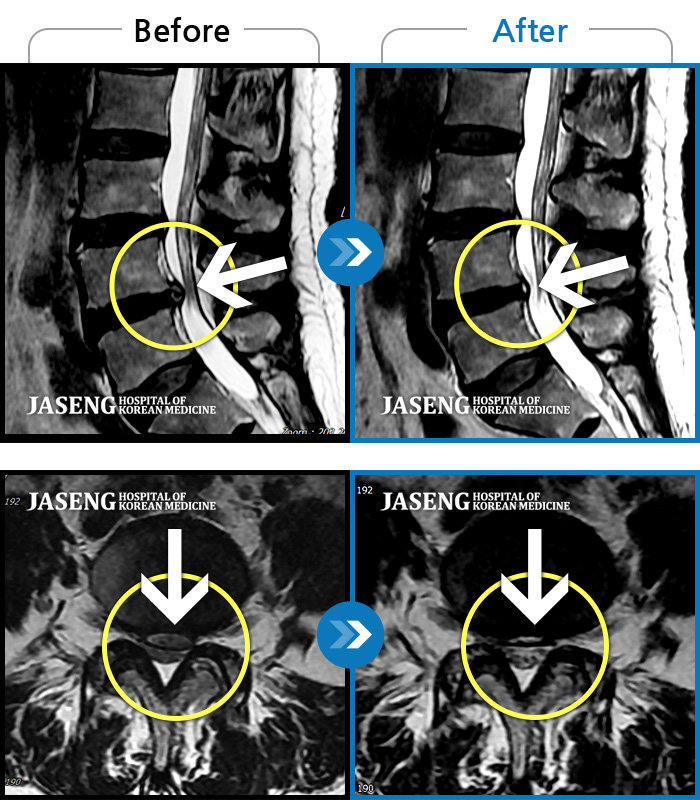

MRI ũ ʸ Ȯϼ.